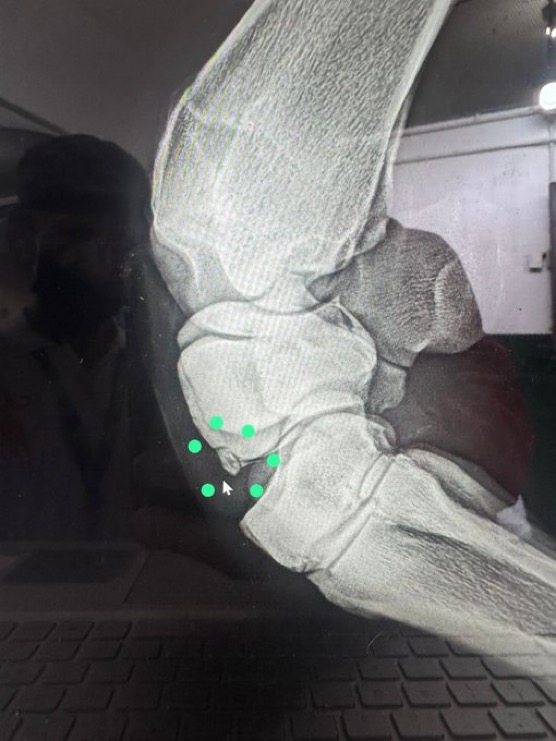

MAPLE GROVE tuvo mejor remate y los pasó de viaje para ganar de manera sensacional dando una sorpresa histórica convirtiéndose en el primer perdedor (llegó de 6-0) en ganar el segundo paso de la Triple Corona Venezolana. Recordamos a DIEGOL en 2017, HARRIMAN en 2009, PAPA LUCAS en 2006 que lo lograron como ganadores de 1. Otro éxito para Germán Rojas quien nunca le perdió la confianza y doblete clásico para el jinete Jonathan Aray. Del Haras Montesano, satisfacción para José Luis Miglietti, otra vez los VACATION al tope en las coronas y 4to ganador clásico de MAGNOLIA MOON, hija de MALIBU MOON, que antes dio en el Paumar a ABUELO ADIB, SCOOBY y CATIRA DANIELA. La gente del Stud Excelso celebró su primer clásico en La Rinconada, venía de una jornada de 4 triunfos el día anterior en Valencia donde ejercen supremacía. EL REALAMPAGO, informó Ricky D´Angelo el lunes, se fracturó el carpo radial, 6 semanas fuera de cancha luego de la operación que será mañana miércoles. De momento, les decimos que en 23 de las 69 ediciones completas de la Triple Corona han ganado ejemplares diferentes en las 3 carreras. Otro dato interesante, DIXIE TEMPO la abuela de MAPLE GROVE corrió 58 veces desde los 2 hasta los 6 años, ganó 8 y 10 segundos. Ilustramos con foto de la fractura de EL RELAMPAGO publicada por su entrenador Ricky D´Angelo